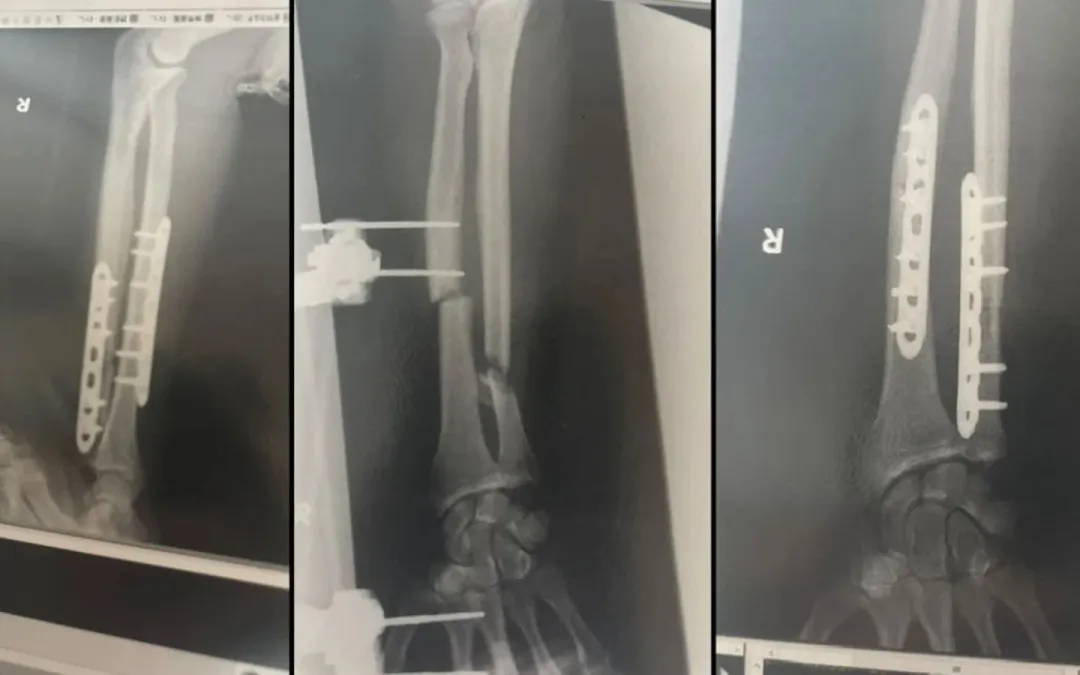

目前他已经做了3次手术。

最近一次是4小时的髋骨移植,因为熊的一口咬掉了他的一大块手臂骨头。

现在,他的手臂里有两块金属钢板,每天有4名护士轮流照顾。